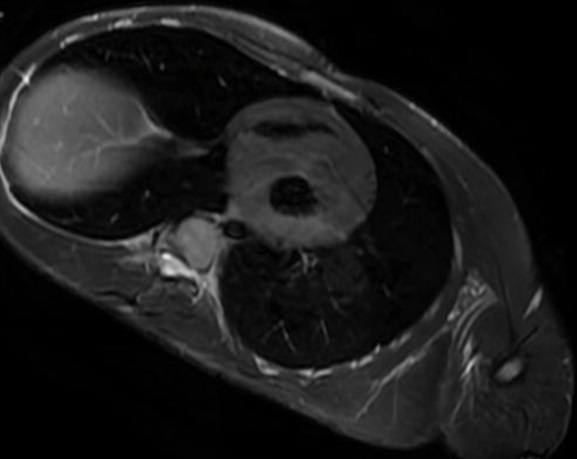

Ante dicho soplo, de características aparentemente funcionales, se realiza un electrocardiograma en el centro de salud (Figura 1), en el que destaca una taquicardia sinusal a 150 lpm, desviación del eje a -30°, QTc de 0,49 segundos y signos de hipertrofia ventricular izquierda (HVI).

| Figura 1. Electrocardiograma realizado en el centro de salud con signos de hipertrofia ventricular izquierda |